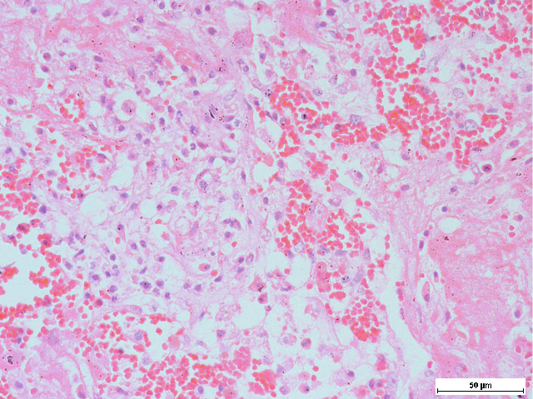

Presence of alveolar macrophages and neutrophils, intermixed with fibrin along with haemorrhage in the lungs